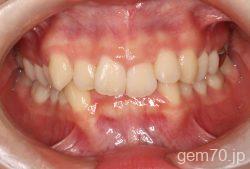

主訴)前歯のかみ合わせが深い

診断)過蓋咬合

年齢)21歳

使用装置)マルチブラケット装置(セラミックブラケット)

治療方法)4|4/4|4

治療期間) 2年8ヵ月 通院回数 32回